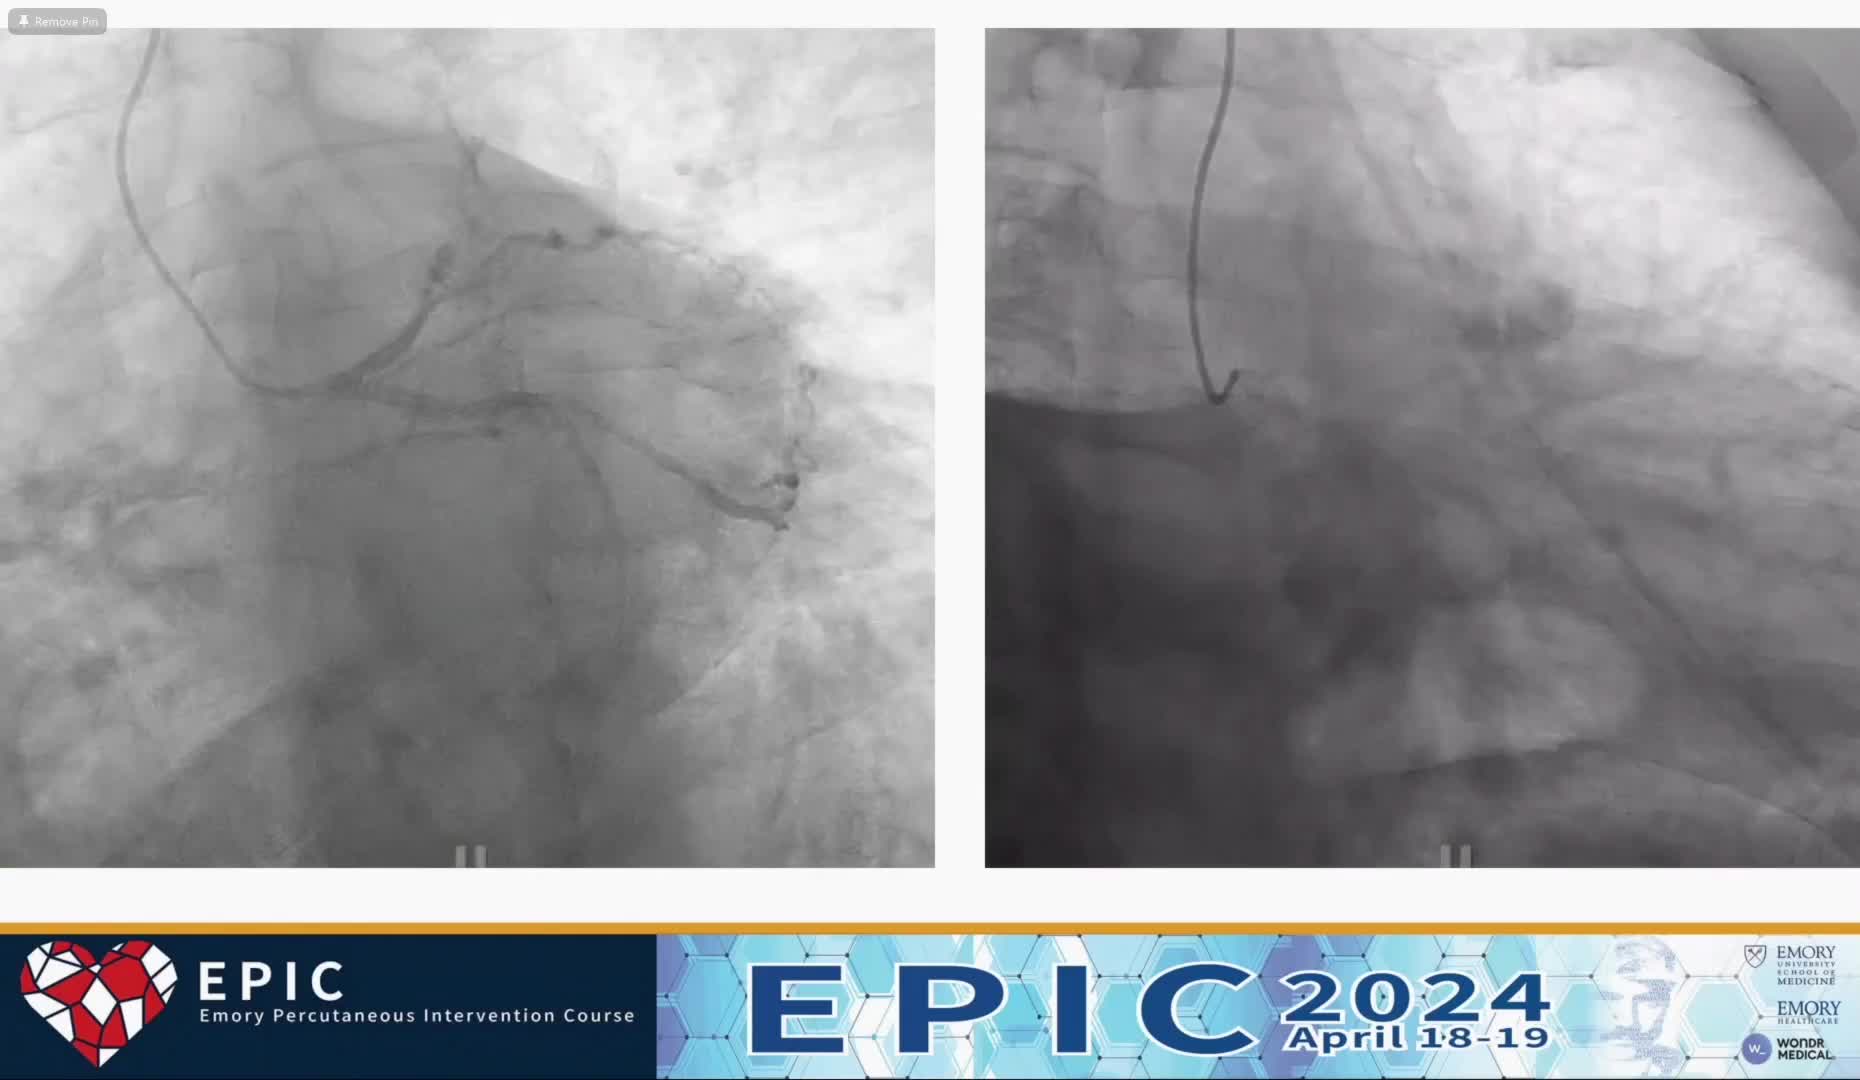

Case 4 - AD CTO PCI with Mechanical Circulatory Support